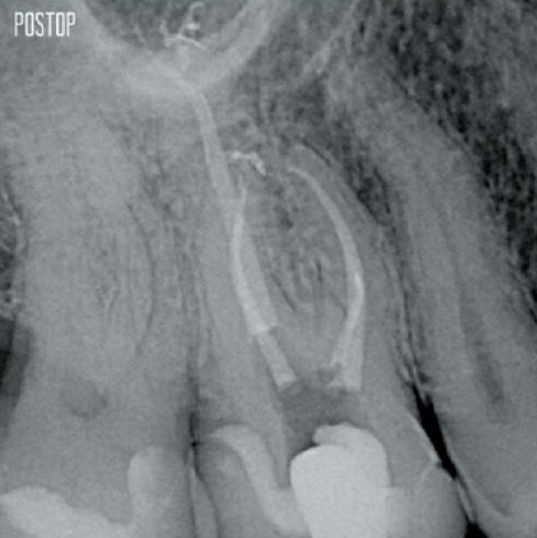

Fotos cortesía del Dr. Ahmed Salman

Más conservación de dentina. Se garantiza la conformación, irrigación y obturación adecuadas.

Sí, las puntas de gutapercha Conform Fit® TruNatomy están diseñadas para coincidir perfectamente con las preparaciones realizadas con las limas TruNatomy y garantizar una obturación óptima.

La flexibilidad de la aguja de irrigación TruNatomy le permite progresar apicalmente en conductos curvos por debajo de 12 mm.